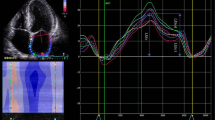

LAS reservoir (LASr), conduit (LAScd), contractile (LASct), and LV global longitudinal strain (GLS), were measured by two-dimensional speckle tracking echocardiography technique using a frame rate from 40–80/s. Biplanar calculation of LAS was based on the ASE/EACVI standardization document [13]. As recommended by this task force, the endocardial border was manually traced and the regions of interest were adjusted to cover the myocardium (Fig. 1) according to previously described steps for nondedicated software [14]. These results were displayed on the following tables.

Besides, more recently, novel dedicated LA tracking tool has been available in the software, so that an additional biplanar analysis of LAS was also performed for all cases (Fig. 2). This dedicated tool provided automated recognition of the chamber based on initial landmarks (two points to mark mitral ring and one point for LA roof). Diastolic function analysis was performed according to the 2016 ASE/EACVI guidelines [6]. Pulmonary vein Doppler was also acquired and analyzed.